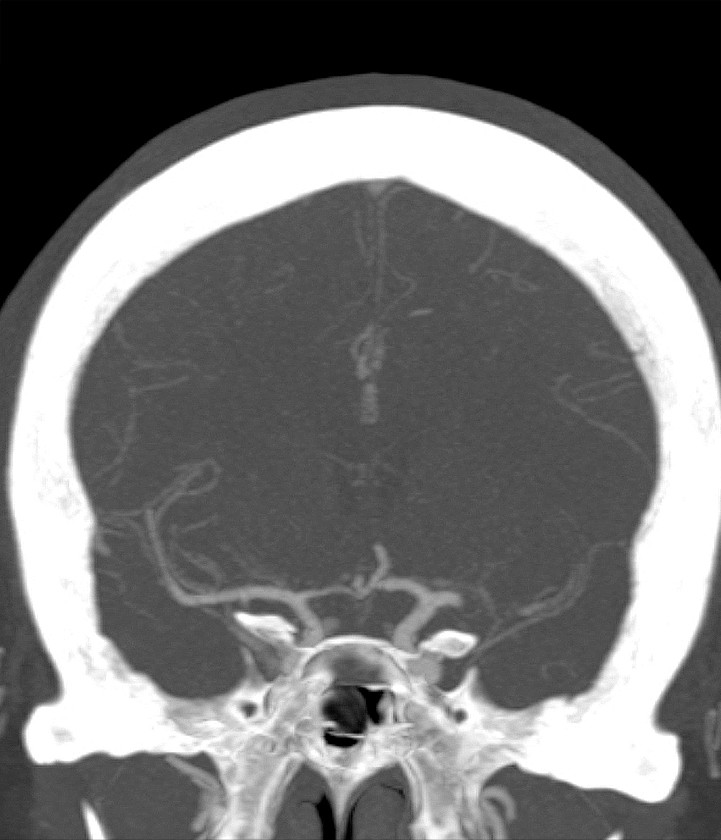

Myren-Svelstad S, Hammer TA, Idicula TT. Early thrombectomy of a proximal middle cerebral artery occlusion leading to complete recovery with no infarct. Case Rep Neurol 2017; 9: 76 - 80. [PubMed][CrossRef]

Vi vil takke for en fin kasuistikk som til fulle viser hvilket potensiale mekanisk rekanalisering (trombektomi) har ved cerebral storarterieokklusjon. Antall som må behandles for én pasient skal komme gjennom et hjerneinfarkt med mindre grad av funksjonshemming (Number Needed to Treat, NNT), er 2,6. I Norge gjennomføres trombektomi per dags dato ved fem sykehus, og to nye sykehus skal starte med trombektomi fra neste år.

De fem store randomiserte trombektomi-studiene inkluderte hovedsakelig pasienter med større nevrologiske utfall. De fleste studiene hadde NIHSS-skår på minst 6 som nedre grense mens MR CLEAN-studien inkluderte pasienter med NIHSS-skår på minst 2 (1). Etter publiseringen av disse studiene er det blitt rutine å trombektomere pasienter også med lettere utfall. I metaanalysene hadde 581 pasienter NIHSS-skår < 8 og 413 pasienter NIHSS-skår ≤ 5. De som ble behandlet med trombektomi, hadde signifikant bedre funksjonsnivå etter 3 måneder sammenliknet med dem som kun fikk medisinsk behandling (2, 3).

Ved St. Olavs Hospital synes man å ha en meget konservativ utvelgelse av pasienter for trombektomi. Forfatterne skriver at behandlingen vanligvis ikke gjøres ved NIHSS-skår < 10. Vi mener i overenstemmelse med publiserte metaanalyser at en slik høy grense for intervensjon gjør at endel pasienter går glipp av svært viktig akuttbehandling. Målet med trombektomi er å begrense skadevolumet i hjernen, ikke å reperfundere et hjernevolum som allerede er nekrotisk. Ved de andre trombektomi-sentrene i Norge vektlegges derfor CT/MR penumbra-vurdering, kollateralsirkulasjon og eventuelt diffusjonsfunn på MR sterkere enn selve NIHSS-skåren når indikasjonen for trombektomi stilles. I OUS-materialet fra 2017 hadde 39 av totalt 120 pasienter (32,5 %) NIHSS-skår < 10 på indikasjonstidspunktet (abstrakt presentert på Nevrodagene 2018 ved B. Enriques og medforfattere). Disse hadde klinisk og radiologisk et stort truet penumbravolum. Ved å bruke høy NIHSS-skår som indikasjon og ikke en individuell fysiologisk tilnærming vil trolig for få pasienter bli behandlet og det samlete resultatet etter trombektomi bli vesentlig dårligere enn det kunne ha vært.

Vi takker Anne Hege Aamodt og medarbeidere for en hyggelig og viktig kommentar. Beklageligvis ligger pasientkasuistikken noe tilbake i tid, utarbeidelse av manuskript likeså. I Trondheim benyttes CT/MR for vurdering av penumbra og kollateralsirkulasjonen vektlegges. At NIHSS-skår ikke kan benyttes som indikasjon alene er selvsagt, og denne misforståelsen beklager vi. Samtidig bør det være et visst nevrologisk utfall før en invasiv prosedyre utføres. Ved St. Olavs hospital gjøres i dag normalt ikke trombektomi ved NIHSS-skår ≤ 5, men alle pasienter som kan være kandidat til trombektomi, får en individuell vurdering, også de med lavere NIHSS-skår.